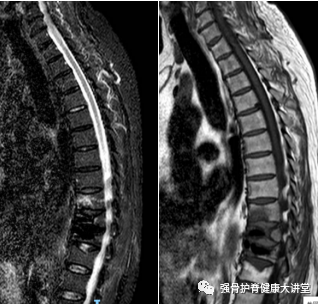

一个多月前,我们收治1例多次PVP(T10、T11)术后仍有腰背痛的患者,经查:骨密度:-2.2(≥-1.0为正常),血沉:23 mm/h,CT提示T9椎体前下方骨折,MRI提示:T9椎体信号异常,T10、T11信号不均。

胸椎核磁可见T9椎体前下方区域炎性浸润

综合影像资料及病史分析,脊柱感染可能性较大。